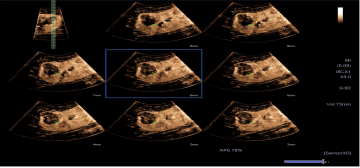

4D造影谐波成像技术(4D CHI):

1. 可应用于妇科领域,包括4D子宫输卵管造影;

2. 具备多切面显示功能,像观察CT片一样,更为全面了解病变的灌注情况。